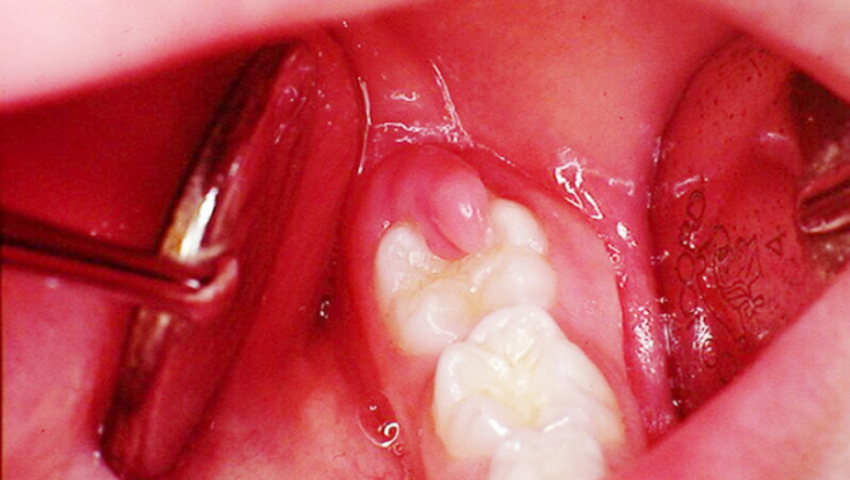

Điều trị lợi trùm răng khôn phương pháp tiểu phẫu

Với những tình trạng viêm nhiễm nặng, nha sĩ sẽ chỉ định thực hiện tiểu phẫu cắt lợi trùm đối với những trường hợp răng khôn mọc thẳng. Điều này giúp giải phóng không gian cho răng khôn có thể tiếp tục mọc lên, quá trình hậu phẫu người bệnh có thể bị chảy máu, rỉ máu, thông thường tình trạng này sẽ ổn định sau khoảng 1 đến 2 tuần.

Với những tình trạng viêm nhiễm nặng, nha sĩ sẽ chỉ định thực hiện tiểu phẫu cắt lợi trùm đối với những trường hợp răng khôn mọc thẳng.